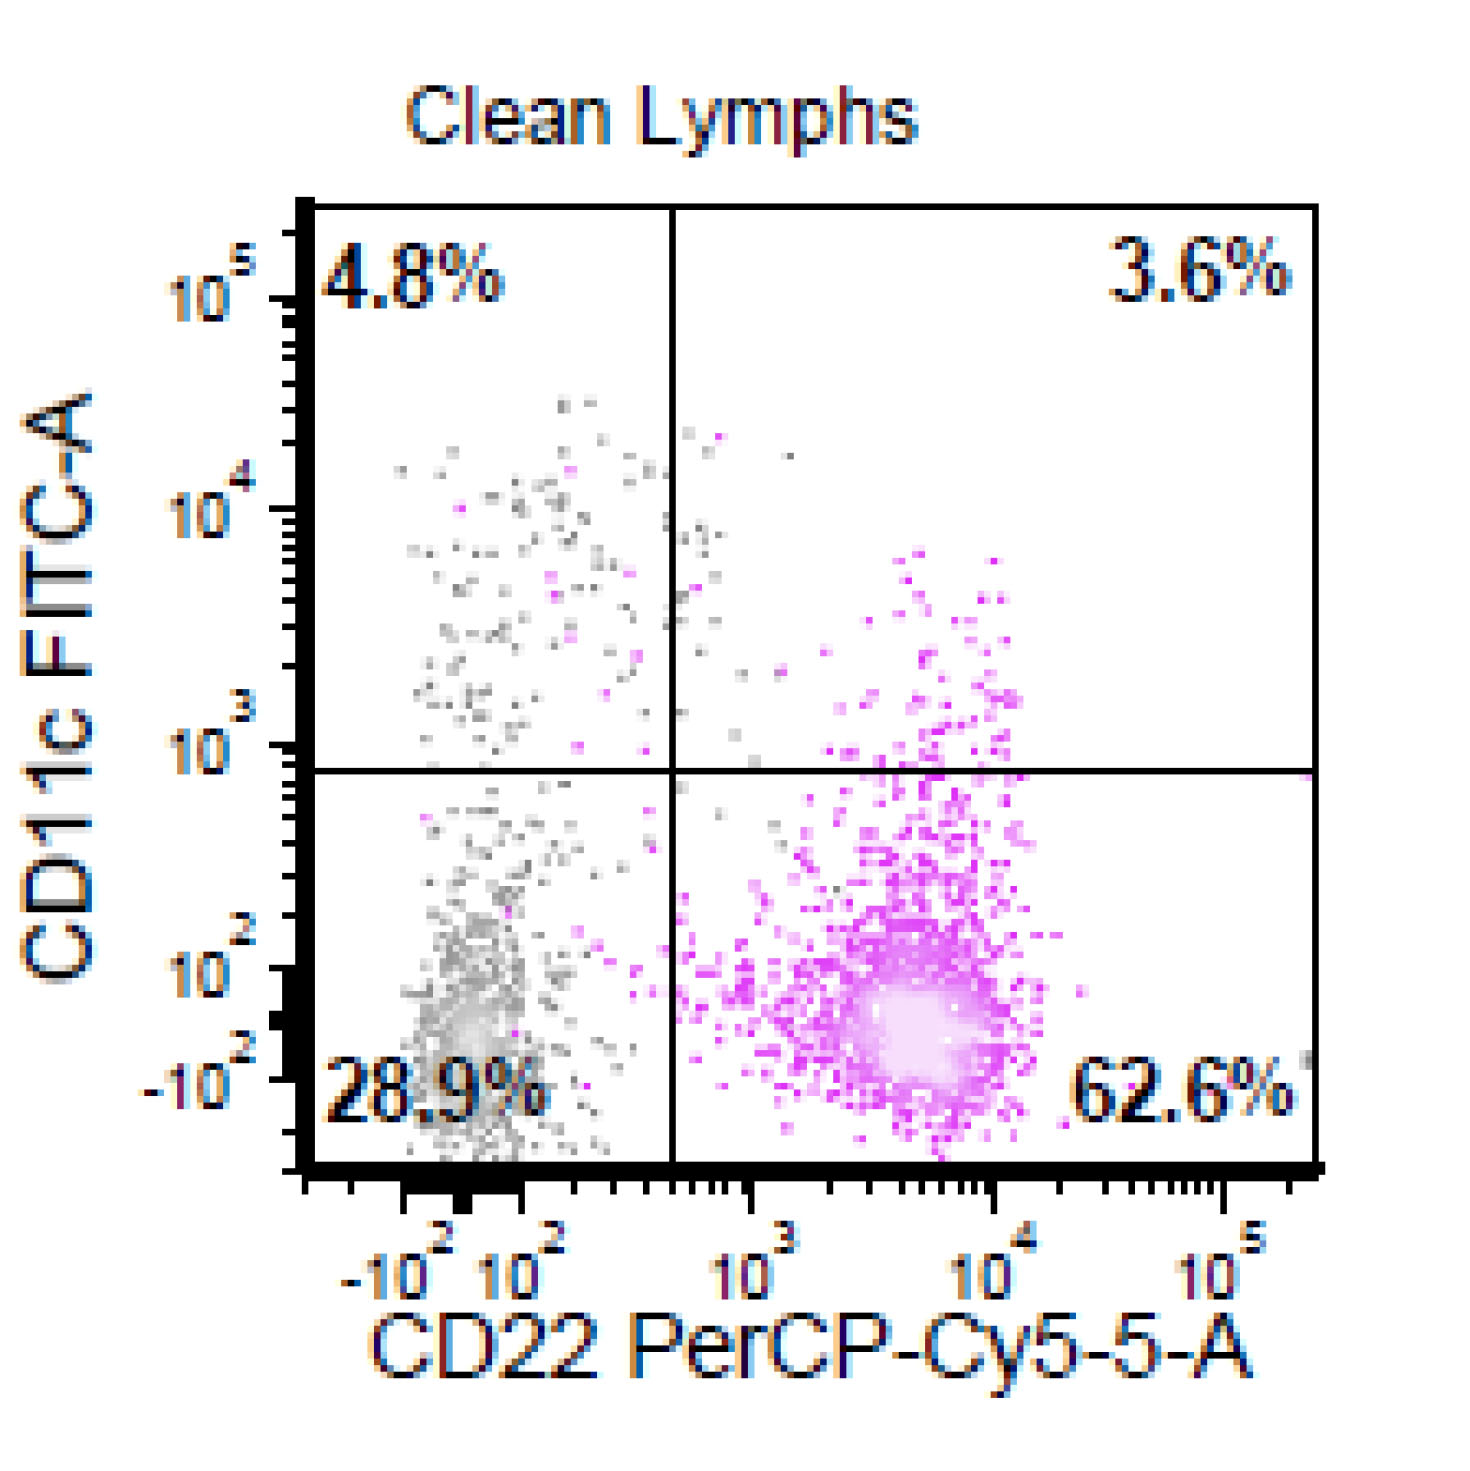

Flow cytometry description

- CD5+, CD19+, CD20+, CD22+, CD79b+, FMC7+

- Monotypic Ig (high level expression of surface light chains)

- CD11c variable, CD43 variable, CD200 variable

- CD3-, CD10-, CD23-

- Rare cases have atypical immunophenotype:

- CD5- or CD10+, CD200+ or CD23+ (dim ~10%)

Flow cytometry images

Flow cytometry immunophenotyping detected a lambda restricted B cell population positive for CD10, CD19, CD20, CD22, CD38, CD79b; while negative for CD5, CD11c, CD30, CD43, CD44, CD200 and kappa light chain.

- This is the concurrent fine needle aspiration flow cytometry of the lymph node in a 70 year old man with lymphadenopathy. Cytology smears show intermediate to large lymphoid cells in a necrotic background. What is the most probable preliminary diagnosis before further work ups on the excised lymph node?

- Mantle cell lymphoma